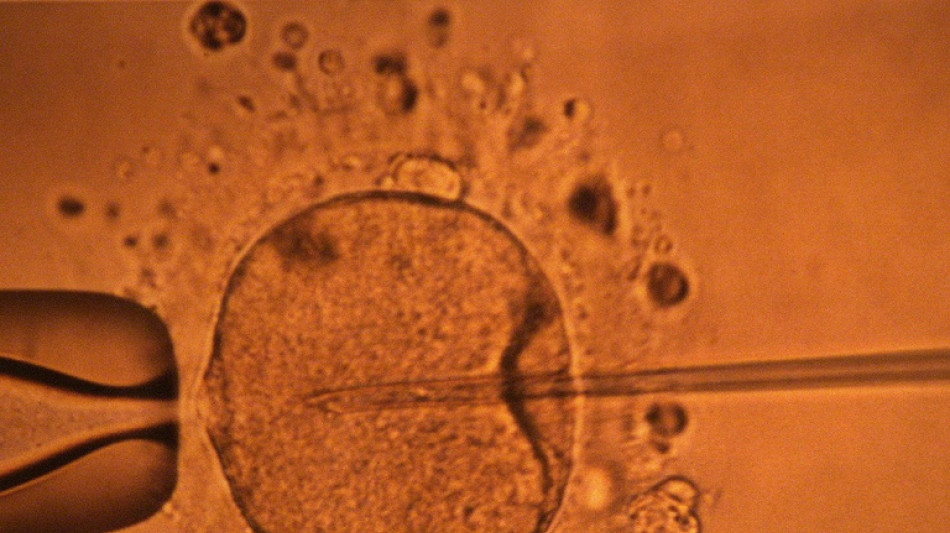

La concentración de espermatozoides, uno de los factores de la fertilidad masculina, disminuyó significativamente en todo el planeta en las últimas décadas, según un estudio publicado el martes.

La cantidad de espermatozoides es uno de los factores que afectan a la fertilidad masculina, pero no es el único.